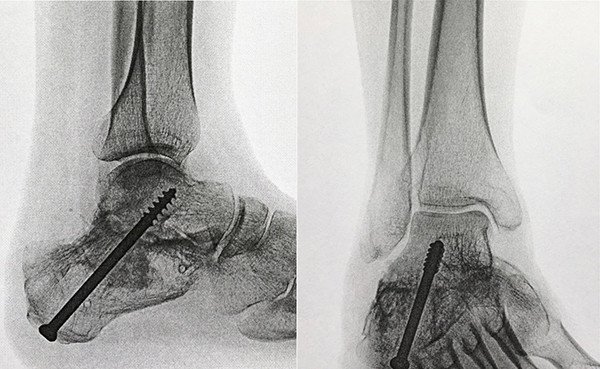

Nach einer kurzen Bedenkzeit willigte die Patientin ein, Abbildung 5 zeigt das postoperative Ergebnis. Die Nachbehandlung wurde unter Anlage einer Unterschenkel-Orthese durchgeführt, mit welcher für einen Zeitraum von 6 Wochen lediglich eine Teilbelastung an Unterarmgehstützen erlaubt war.